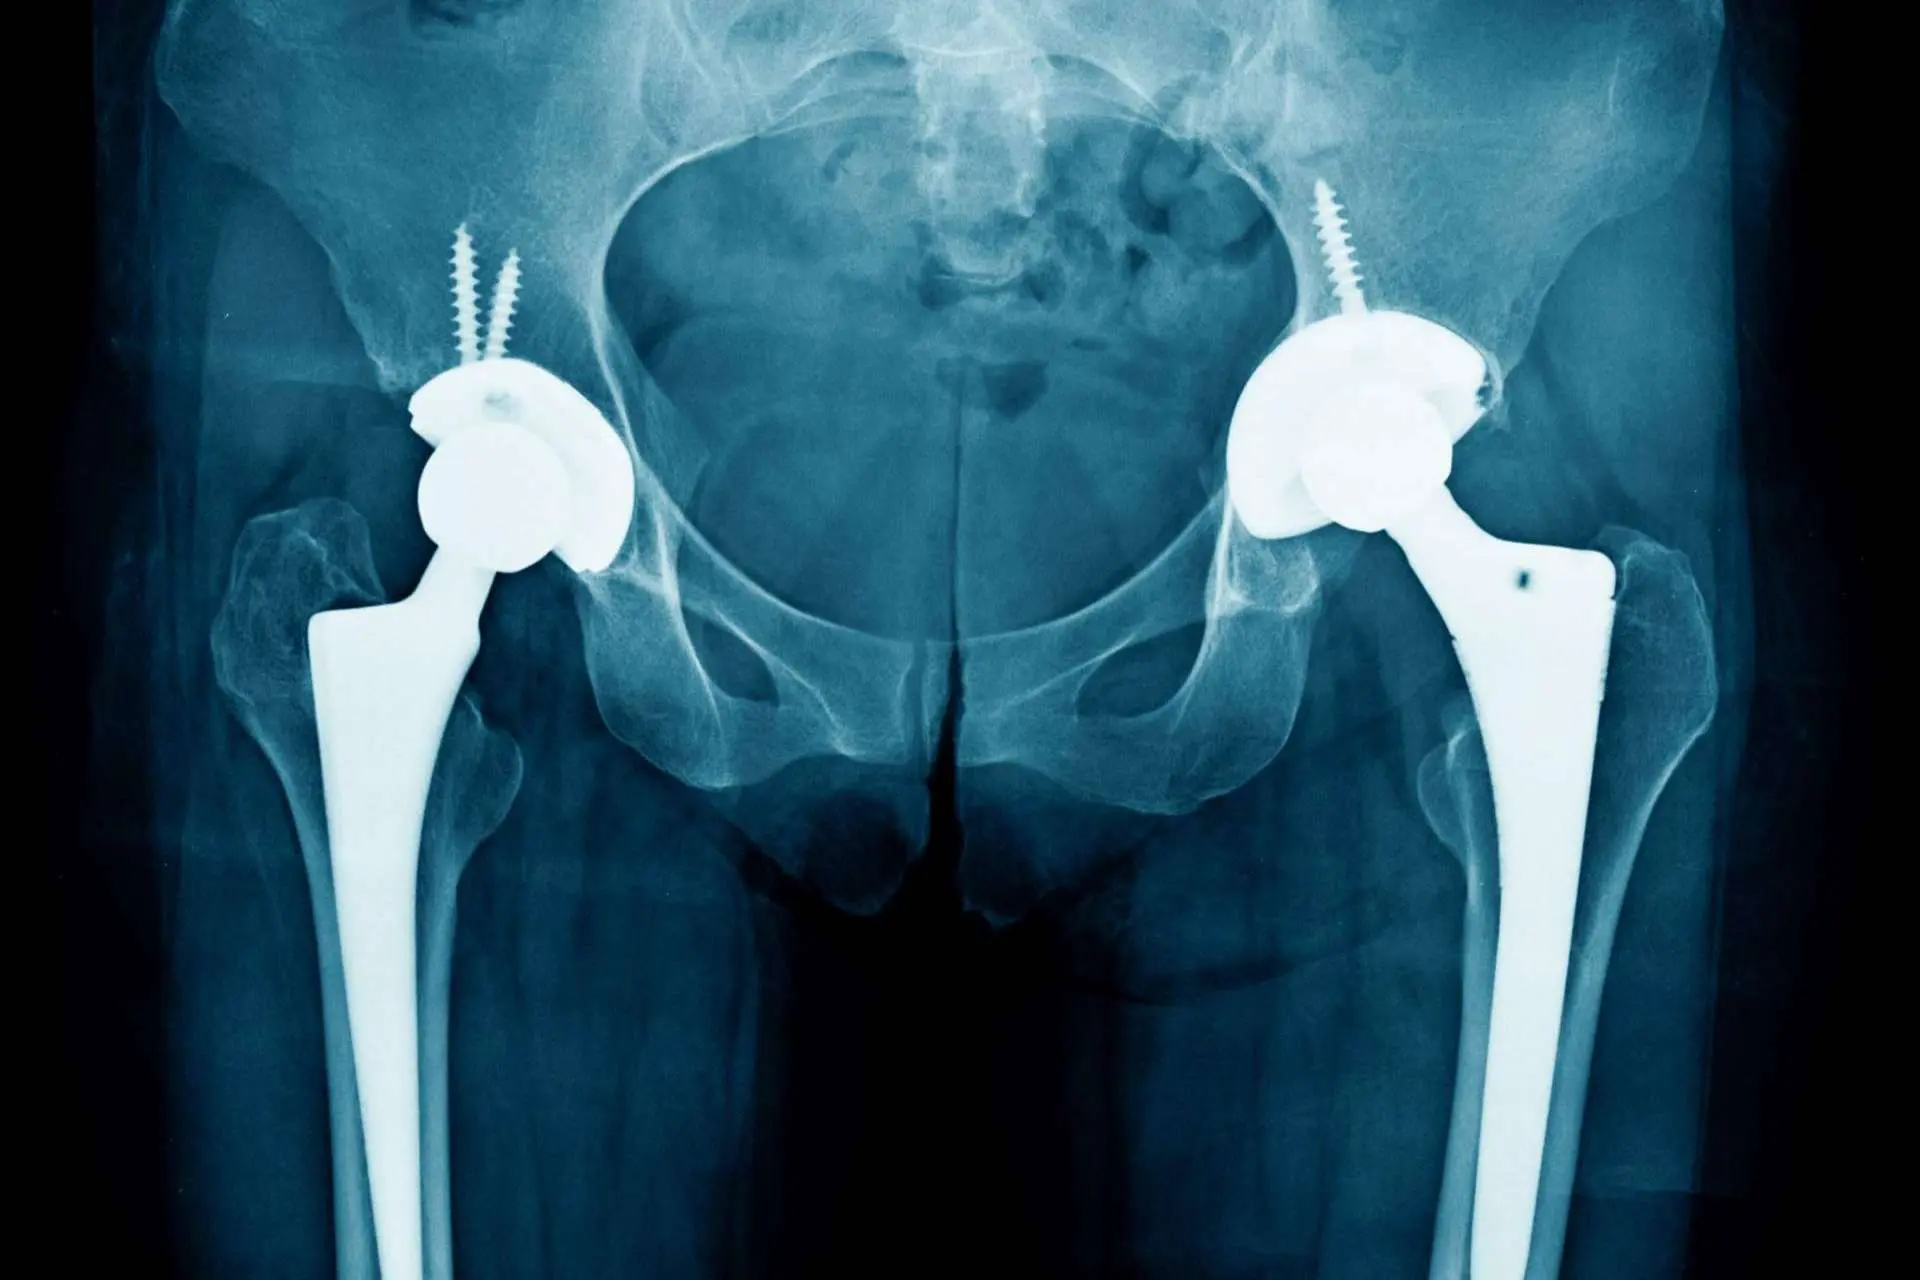

Sobre la artropatía degenerativa explican que sus causas no están del todo claras. Pueden ser generadas por lesiones, accidentes o sobrecargas persistentes que van acumulando un deterioro progresivo en las articulaciones. También se relaciona con posturas incorrectas que algunas personas tienen de nacimiento y con factores hereditarios relacionados con la genética familiar.

La artropatía degenerativa es una patología crónica cuyos síntomas se manifiestan con rigidez y sensación de tensión en la articulación afectada. También son frecuentes los crujidos o chasquidos al moverse y la sensibilidad aumentada cuando el paciente se enfrenta a climas húmedos. Cómo es lógico, en muchos casos, el síntoma más incómodo suele ser el dolor.